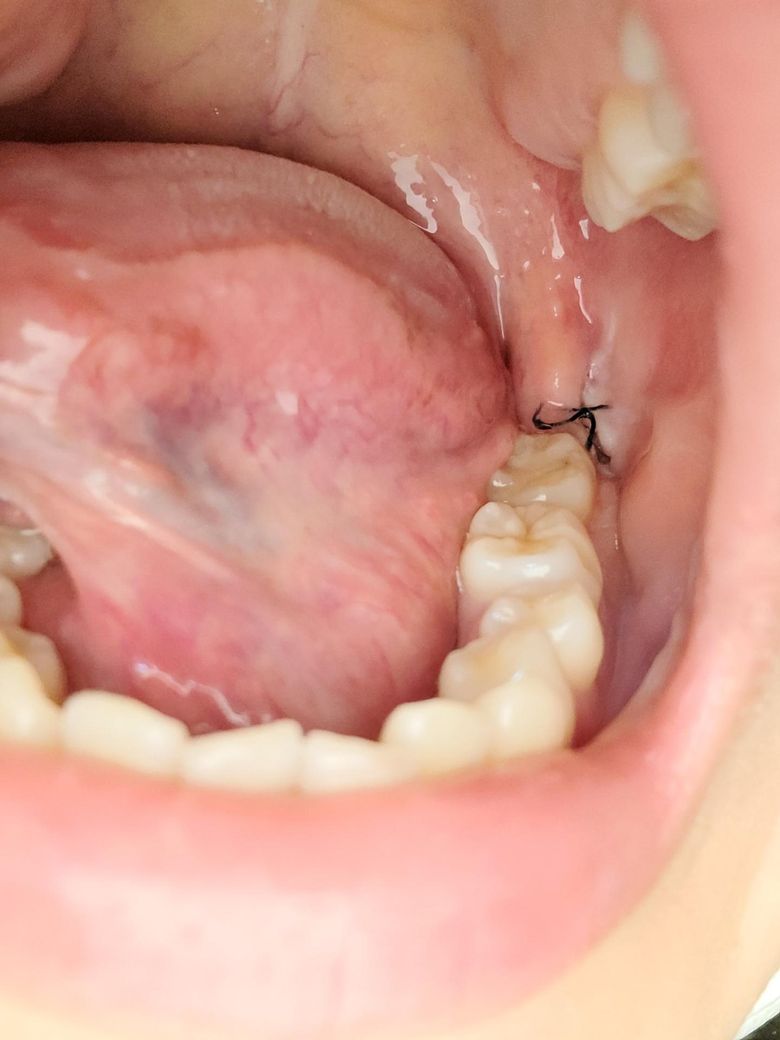

매복사랑니 화요일에 빼고 지금 3일정도됬는데 사진으로 보다시피 하얀색뭐가있어서요 이게 드라이소켓?이라는건지 아니면 그면 음식물이 낀건지 어제도 있길래 이쑤시개 로 뺐더니 없어지긴하더라고요? 건드리면 안됬던건지 궁금해요!

드라이소켓은 발치부위 상처에서 피가 딱지로 굳지 못하여 발생하고 약으로 조절할수 없는 통증이 동반됩니다. 발치 부위에 낀 음식물은 제거해주면 됩니다. 건강하세요.

딱히 드라이소켓의 양상은 아닌 것으로 보입니다. 아마도 이물질이었을겁니다. 이쑤시개는 자극이 되니 그거보다는 물가글해서 음식물찌꺼기 제거해주세요